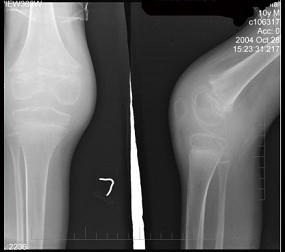

问题 10岁男性患者,左膝关节反复肿胀,活动受限,伴低热2年,经抗炎治疗效果不明显,行左膝关节摄片如图示,最佳诊断是 ( )

选项 A、左膝化脓性关节炎 B、左膝关节肿瘤 C、左膝关节结核(骨型) D、左膝关节结核(混合型) E、左膝关节结核(滑膜型)

答案 E